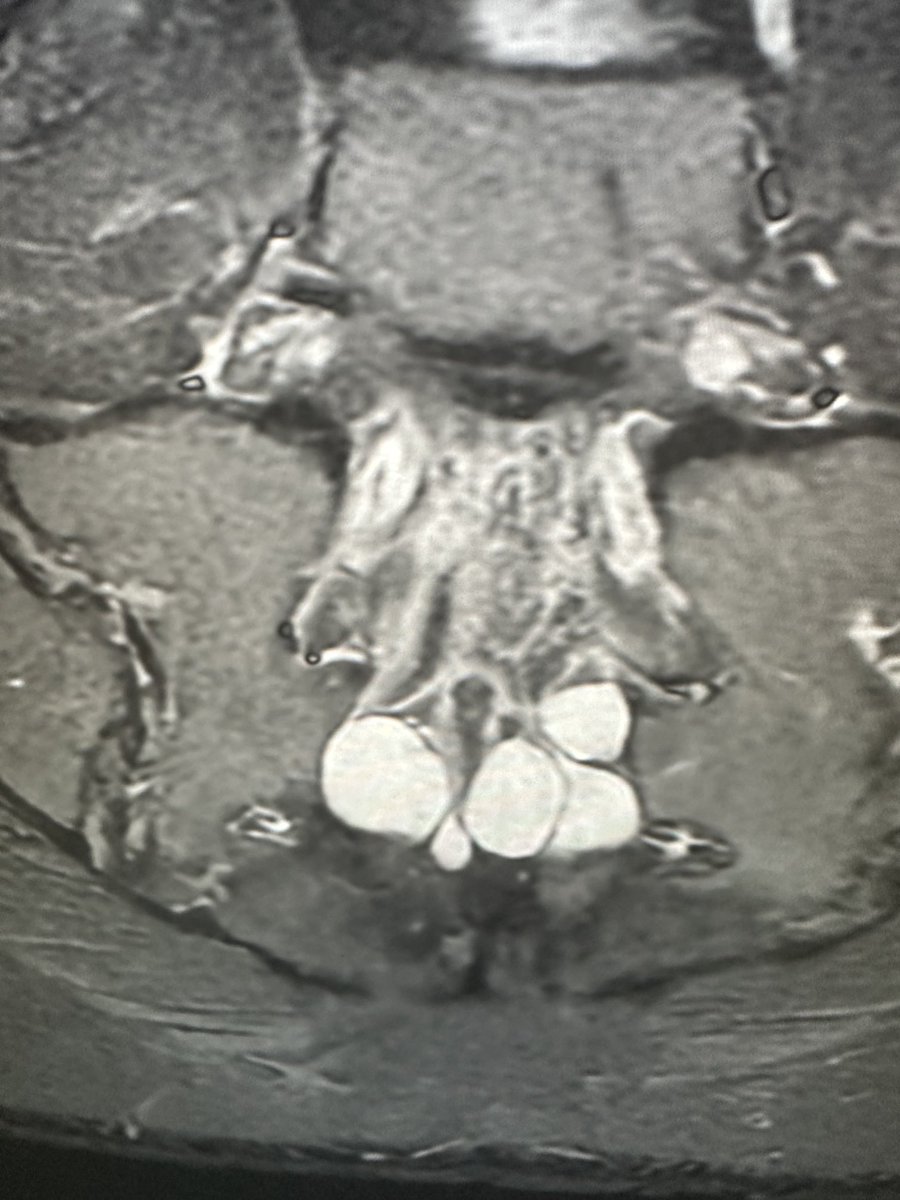

An exciting take on brachial plexopathy through a clinical Radiologist perspective! Followed by approach to muscle edema on MRI!! Do plug in and indulge! #FoamMed #mskrad #radiology #Radres #radiologyresidents